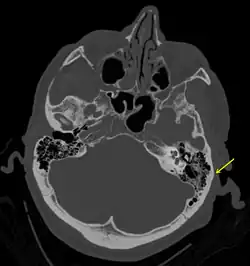

En basisfraktur beskriver et brud på den "underste" del af kraniet – den del af kraniekisten, hjernen kan siges at hvile på. Det er en forholdsvis sjælden fraktur, idet den kun tegner sig for ca. 4% af kraniebrud.[1][2] En basisfraktur er en alvorlig tilstand, idet der er risiko for direkte påvirkning af nærtliggende hjernevæv, ligesom der er risiko for at lædere hjernehinden, så der tabes hjernehindevæske. Dette kan vise sig ved at patienten får et flåd af klar væske fra enten øre eller næse.[3] En basisfraktur vil også kunne medføre en blødning, der viser sig som et brillehæmatom, på engelsk "raccoon eyes", idet blodet kun kan lægge sig i det bløde væv omkring øjnene.